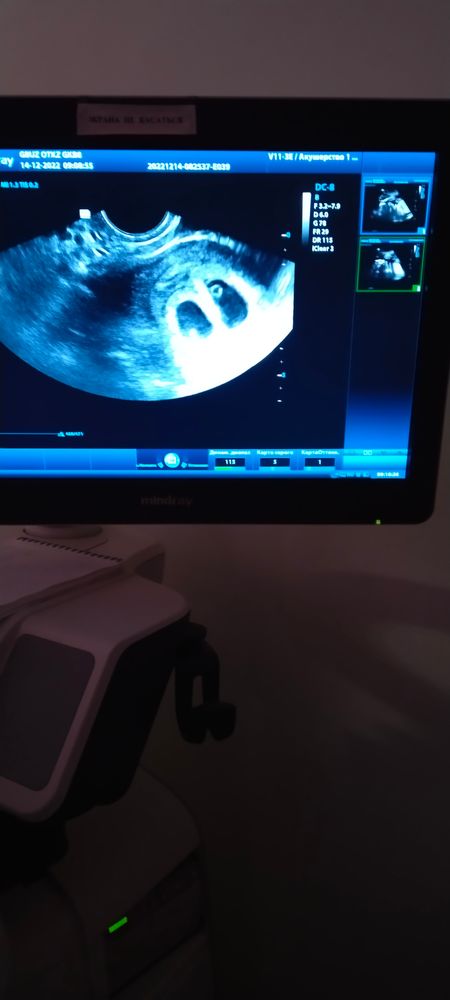

14 декабря при первом УЗИ на сроке 7 недель оказалось,что малышей будет сразу двое.

....Утро после после дежурства,я,лёжа на кушетке,смотрю на экран ,вижу одно плодное яйцо ,озадаченное лицо врача-узиста и рядом ещё одно.Тут наши взгляды встретились-двойня!Да,ответила врач,двойня,у каждого свой домик.Это было так мило...